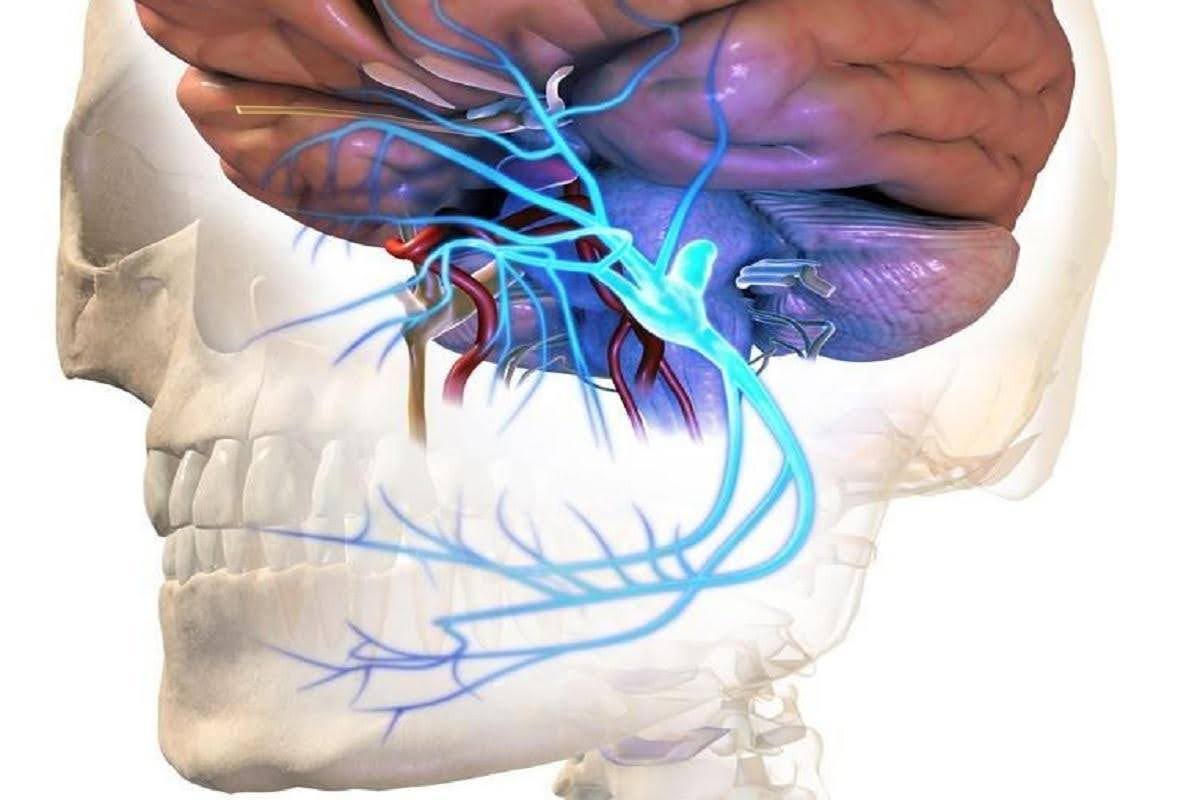

Neuralgia del Trigémino: Una explicación clara y tranquilizadora

## ¿Qué es la neuralgia del trigémino?La neuralgia del trigémino es un trastorno del nervio trigé...